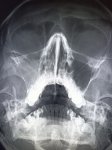

IMG20251016100939.jpg

Найдите поломку!

>>325598813

что за пятно в мозге?

>>325598844

Это дырка в кости же

Аноним 16/10/25 Чтв 08:58:50 #15 №325599636

Аноним 16/10/25 Чтв 09:07:34 #18 №325599870

бля, тут какая то и слева и справа огромные пиздецомы

Средние пиздецомы же